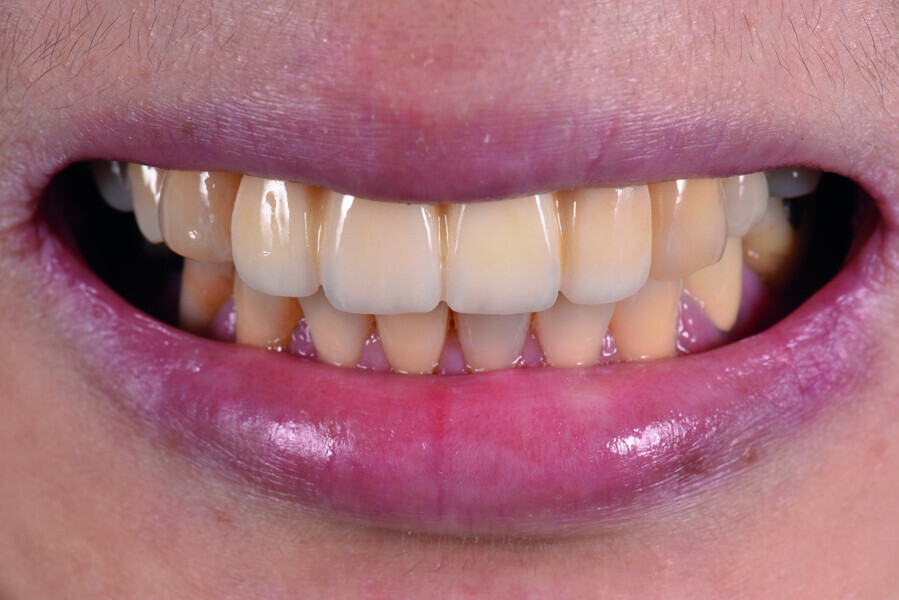

Fig. 9: Patient smiling three months post-op.